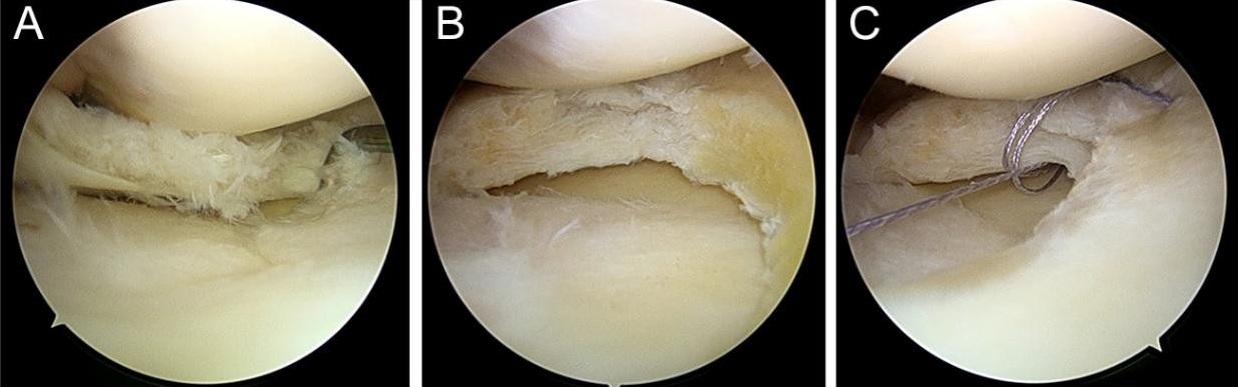

The patient underwent right knee arthroscopy under spinal anesthesia, with the finding of an incomplete type medial discoid meniscus and a complex tear of the posterior horn. Saucerization of the central discoid element and partial medial meniscectomy of the posterior horn were performed. Two all-inside sutures with a non-absorbable stitch were thus applied to repair the complex tear of the posterior horn (Fig. 3).

Figure 3: Arthroscopic findings of right knee: (a) incomplete-type discoid medial meniscus with complex posterior horn tear. (b) Partial meniscectomy with saucerization. (c) All-inside sutures repairing radial and horizontal tears.